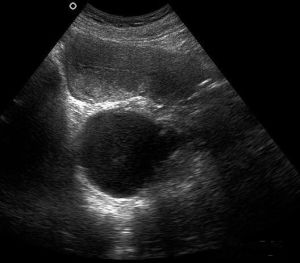

卵巢在排卵後形成黃體,正常成熟黃體直徑2~3cm。若黃體腔內有大量的積液,使腔的直徑超過3cm以上者則稱黃體囊腫。黃體囊腫破裂可發生於已婚或未婚的婦女,...